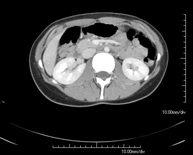

- Abdomen y pelvis- TC Abdomen Prueba diagnóstica que consiste en obtener imágenes del abdomen de alta definición anatómica (hígado, vesícula biliar, vía biliar, páncreas, bazo, estómago, intestinos, riñones, estructuras vasculares, vejiga, útero y ovarios, etc.) mediante el empleo de un equipo de TC (Tomografía Computarizada). Dichas imágenes se estudian posteriormente en una estación de trabajo que permite reconstrucciones bidimensionales en diferentes planos del espacio, y también reconstrucciones 3D (volumétricas). La mayoría de estudios requieren el empleo de contraste yodado para mejorar la definición de las imágenes. Prueba diagnóstica que consiste en obtener imágenes del abdomen de alta definición anatómica (hígado, vesícula biliar, vía biliar, páncreas, bazo, estómago, intestinos, riñones, estructuras vasculares, vejiga, útero y ovarios, etc.) mediante el empleo de un equipo de TC (Tomografía Computarizada). Dichas imágenes se estudian posteriormente en una estación de trabajo que permite reconstrucciones bidimensionales en diferentes planos del espacio, y también reconstrucciones 3D (volumétricas). La mayoría de estudios requieren el empleo de contraste yodado para mejorar la definición de las imágenes.

- TC Riñones Prueba diagnóstica que consiste en obtener imágenes bi y tridimensionales del riñón y del sistema urinario de alta definición anatómica mediante el empleo de un equipo de TC (Tomografía Computarizada). Se realiza el estudio antes y después del empleo de contraste yodado en diferentes "fases renales" para una valoración funcional y anatómica (parénquima renal, uréteres, vejiga urinaria, arterias y venas renales, etc.), así como las estructuras adyacentes (vena cava inferior, aorta abdominal, hígado, bazo, etc.). Está especialmente indicado ante la sospecha de lesiones renales, en pacientes con sangre en orina o hematuria, etc. Prueba diagnóstica que consiste en obtener imágenes bi y tridimensionales del riñón y del sistema urinario de alta definición anatómica mediante el empleo de un equipo de TC (Tomografía Computarizada). Se realiza el estudio antes y después del empleo de contraste yodado en diferentes "fases renales" para una valoración funcional y anatómica (parénquima renal, uréteres, vejiga urinaria, arterias y venas renales, etc.), así como las estructuras adyacentes (vena cava inferior, aorta abdominal, hígado, bazo, etc.). Está especialmente indicado ante la sospecha de lesiones renales, en pacientes con sangre en orina o hematuria, etc.